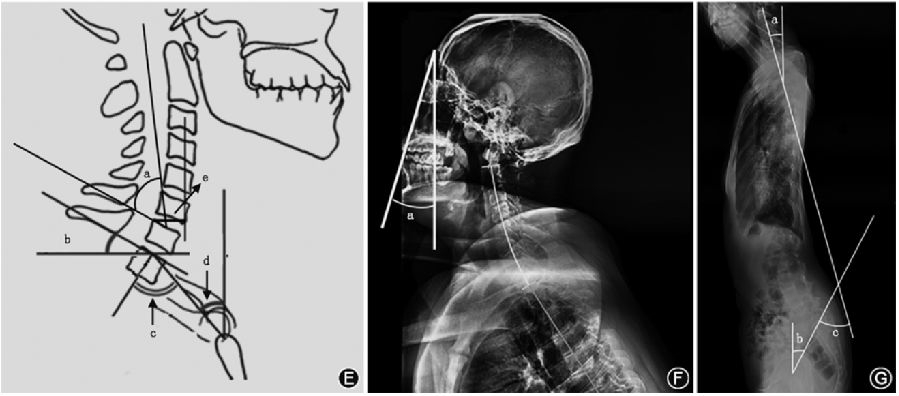

1.CL的测量:测量CL的4种最常见方法包括改良的Cobb方法(mCM)、Jackson生理应力线(JPS)、Harrison后切线(HPT)方法和Ishihara指数(图1A~D)。通过C2法的mCM来获得CL,沿C2和C7下终板绘制两条水平线,分别绘制与前两条线垂直的附加线,两条垂直线所成的角度即C2-7 CL;C1法是从C1的前结节延伸到C1棘突的后缘代替C2的终板作为上参考线来测量C1-7颈椎矢状位Cobb角;用JPS法测量CL时沿C2和C7椎体后壁各画一条直线,这两条直线交角的数值就是CL的测量值。HPT法是从C2到C7所有的颈椎椎体后表面画出平行的直线,然后将所有的节段角度相加得到一个整体的CL角度。Ishihara指数,又称颈椎曲度指数,连接C2的椎体下后端到C7的椎体下后端,从C3、C4、C5、C6椎体下后端分别做垂线,Ishihara指数为4条垂线段的长度和除以C2下后端到C7下后端连线的长度。美国的Janusz等通过对44例患者mCM、JPT和HPT方法的CL测量,认为三种方法均可靠有效,且不同测量者的测量值无明显差异。

(二)颈椎矢状面平衡

矢状面轴向距离(SVA)可以评估全脊柱整体矢状位平衡,颈椎矢状位平衡可以通过CSVA来评估。C2-7 SVA是过C2椎体中心的铅垂线到C7椎体上终板后端之间的距离(图1E)。头部重心(CGH)-C7 SVA(CGH-C7 SVA)是过外耳道前缘的铅垂线到C7椎体后上角的垂线间距离。Iyer等通过双平面成像系统报告了120例无症状患者的C2-7 SVA平均值为21.3 mm,赵文奎等对132名中国无症状成年人测量C2-7 SVA为(18.67±7.96)mm,CGH-C7 SVA为(22.95±12.18)mm。

(三)T1倾斜角

T1倾斜角是T1椎体上终板的延长线与水平线之间的夹角(图1E),T1倾斜角和CL的关系类似于骨盆投射角(PI)和腰椎前凸角(LL)的关系,因为更大的T1倾斜角需要更大的CL来平衡胸部入口和头部的重量。当T1倾斜角在13°~25°时,机体为保持视线水平,可通过上颈椎过伸过屈代偿颈椎的潜在失衡;当T1倾斜角>25°时,颈椎整体容易前倾,重心前移,在重力的作用下,CSVA增大,颈椎曲度发生后凸趋势,导致颈椎矢状位失衡;当T1倾斜角<13°时,存在负平衡。

(四)颈部倾斜角、TIA

TIA是T1椎体上终板中点到胸骨上缘连线和T1椎体上终板垂线之间的夹角(图1E),Lee等认为胸骨、T1肋骨和T1椎体的固定连接导致胸廓入口相对固定,因此,TIA是一个固定的形态学参数。颈部倾斜角是T1椎体上终板中点到胸骨上缘连线与垂直线的夹角(图1E),在无症状的人群中颈部倾斜角保持在44°左右。TIA在数值上等于T1倾斜角和颈部倾斜角相加之和,可以推测较大TIA者为消耗最小能量而获得颈椎水平注视和矢状排列,则需要相应更大的T1倾斜角,进一步CL相应增加。

(五)CBVA

CBVA是一种间接测量水平视线的方法(图1F),可通过临床大体照和X线侧位片上测量患者眉弓到下颌连接线和过眉弓的垂直线对应的角度来获得,当头向下倾斜时,CBVA为正;当头向上倾斜时,CBVA为负;当头部完全竖立并保持中立时,CBVA为零。2016年Iyer等通过对120名无症状成年人进行分析后,其平均CBVA为-1.7°;Song等研究表明CBVA在10°~20°者可获得最佳的结果,可更好地完成室内外活动。

(六)C2PT和SCA

C2PT是C2倾斜角与骨盆倾斜角之和(图1G),C2倾斜角是C2椎体后缘的平行线和垂直方向的夹角,骨盆倾斜角是由S1上终板中点与股骨头中心的连线和铅垂线相交所形成的角度。C2PT角也可测量C2椎体后缘的延长线与股骨头中心到S1上终板中点的连线的延长线夹角。SCA是C7上终板中点和蝶鞍中点连线与C7上终板连线的夹角(图1G),SCA可表示头部前伸姿势,与颈部肌肉能耗密切相关,正常范围为73°~92°。